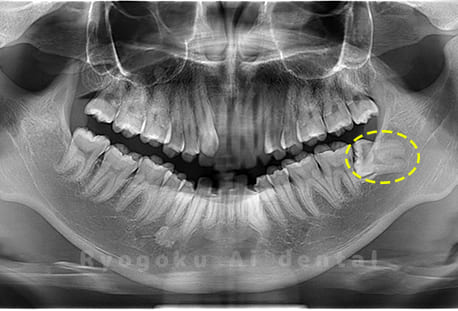

Case01

-

- 原因

- 水平埋伏智歯

- 治療内容

- 下顎の水平埋伏智歯を抜歯

<リスク・副作用>

手術後は痛み、腫れ、痺れなどの副作用が生じる場合があります。